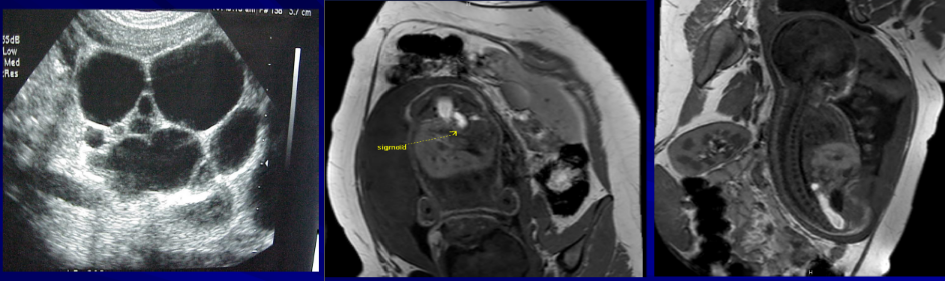

▷ 产前诊断

- 超声 胎腹膨隆;下腹可见“双叶征”;羊水过多

- 胎儿MRI

产后诊断

X线征象:出生12h后进行倒立侧位摄片(时间、体位、按摩、肛门标志)